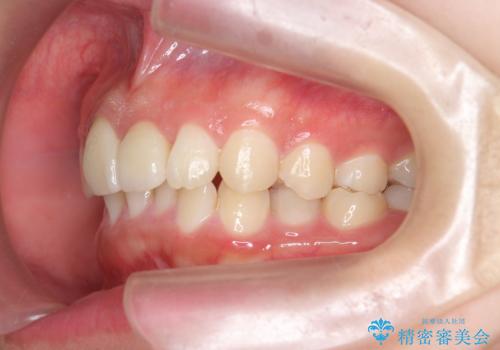

出っ歯をセラミックで治したい

- 前歯の突出を主訴に来院。

矯正治療は絶対したくないとのことでした。

部分矯正なども提示しましたが、早く治すセラミック治療を選択されました。